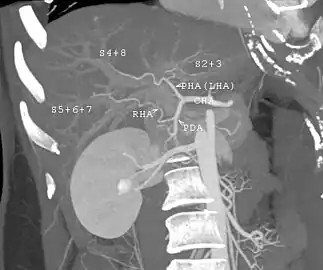

With the recent advances of noninvasive imaging, living liver donors usually have to undergo imaging examinations for liver anatomy to decide if the anatomy is feasible for donation. The evaluation is usually performed by multidetector row computed tomography (MDCT) and magnetic resonance imaging (MRI). MDCT is good in vascular anatomy and volumetry. MRI is used for biliary tree anatomy. Donors with very unusual vascular anatomy, which makes them unsuitable for donation, could be screened out to avoid unnecessary operations.

MDCT image. Arterial anatomy contraindicated for liver donation